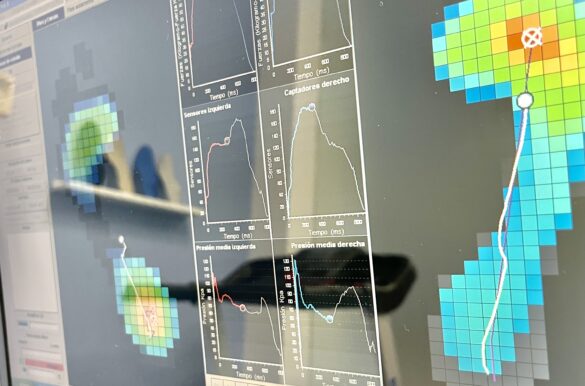

Beneficios del estudio de la pisada Prevención de lesiones y…

Todos y cada uno de los tratamientos que ofrecemos los enfocamos desde un punto de vista podológico y multidisciplinar, en caso de necesidad. Gracias a nuestro amplio conocimiento en biomecanica del pie, abordamos la patología podologica o corporal asociada con la premisa de respetar el correcto funcionamiento del aparato locomotor durante la deambulación, actividades cotidianas, deportivas e incluso laborales.